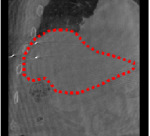

An example of CT/CBCT and MR/CBCT registration results are shown in figures 3 and 4, respectively. For both cases, the CBCT image (first column) was acquired intra-operatively after needle insertions and was employed as a reference for image registration. The pre-operative image is displayed before registration (second column), after PM-EA (third column) and after PM-EA+Evo (fourth column). The occurrence of patch shifts is reported for each spatial direction in panels (m–o): for each histogram, the shift with maximal occurrence is shown by the red dashed line. For panels (a–l), a ROI — manually defined on the CBCT image/encompassing the liver — is shown using red dash lines. Our visualization shows an improved correspondence of the contour of the liver with the manually defined liver boundary when the PM-EA solution is employed (see 3(c,g,k) and 4(c,g,k)). Moreover, an even better correspondence of the contour is observable using the PM-EA+Evo solution (see 3(d,h,l) and 4(d,h,l)).

Trans.

[X-Y]

CBCT

(a)

MRI / No registration

(b)

MRI / PM-EA

(c)

MRI / PM-EA+Evo

(d)

Sag.

[X-Z]

(e)

(f)

(g)

(h)

Cor.

[Y-Z]

(i)

(j)

(k)

(l)

(m)

(n)

(o)